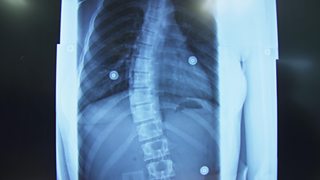

Megan needs important spinal surgery

Duration:

1:31